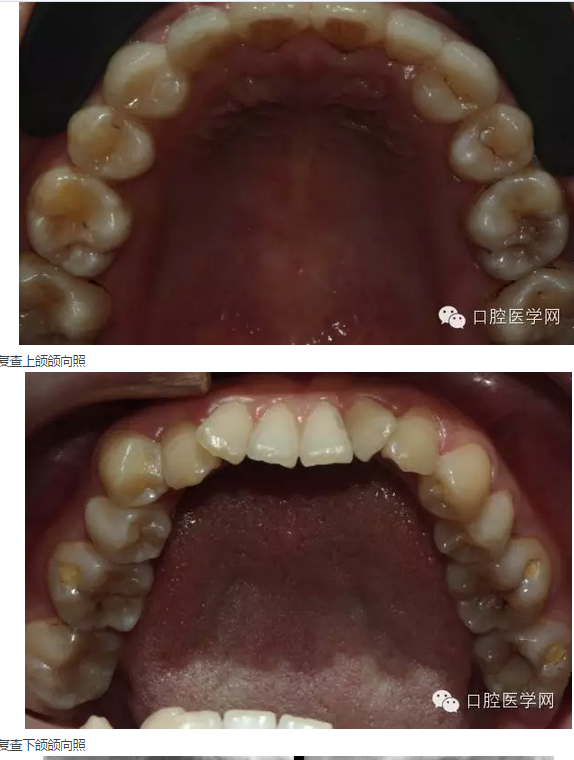

檢查:13、23缺失,后牙前移;14、12-22、24牙冠未及明顯缺損,叩痛(-),不松動(dòng),齦未見明顯異常,覆頜覆蓋關(guān)系大致正常。上前牙散在間隙,咬合時(shí)上下牙之間存在間隙; 12,22錐形牙,尤其12牙體較小(見圖01、02)。余見:下頜牙列較擁擠,44、34稍近中傾斜,44稍偏頰側(cè)。46、36、37頰點(diǎn)隙及37頜面可見陳舊牙色充填物。

術(shù)前下頜頜向照